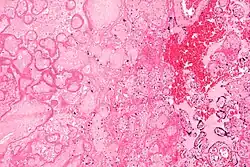

Micrograph of a placental infarct. H&E stain.

A placental infarction results from the interruption of blood supply to a part of the placenta, causing its cells to die.

Small placental infarcts, especially at the edge of the placental disc, are considered to be normal at term. Large placental infarcts are associated with vascular abnormalities, e.g. hypertrophic decidual vasculopathy, as seen in hypertension.[1] Very large infarcts lead to placental insufficiency and may result in fetal death. Placental infarcts are generally detected after birth, although using ultrasound may be a way to notice infarcts prenatally. This method still needs more research and may not be completely effective in noticing infarcts. [2]